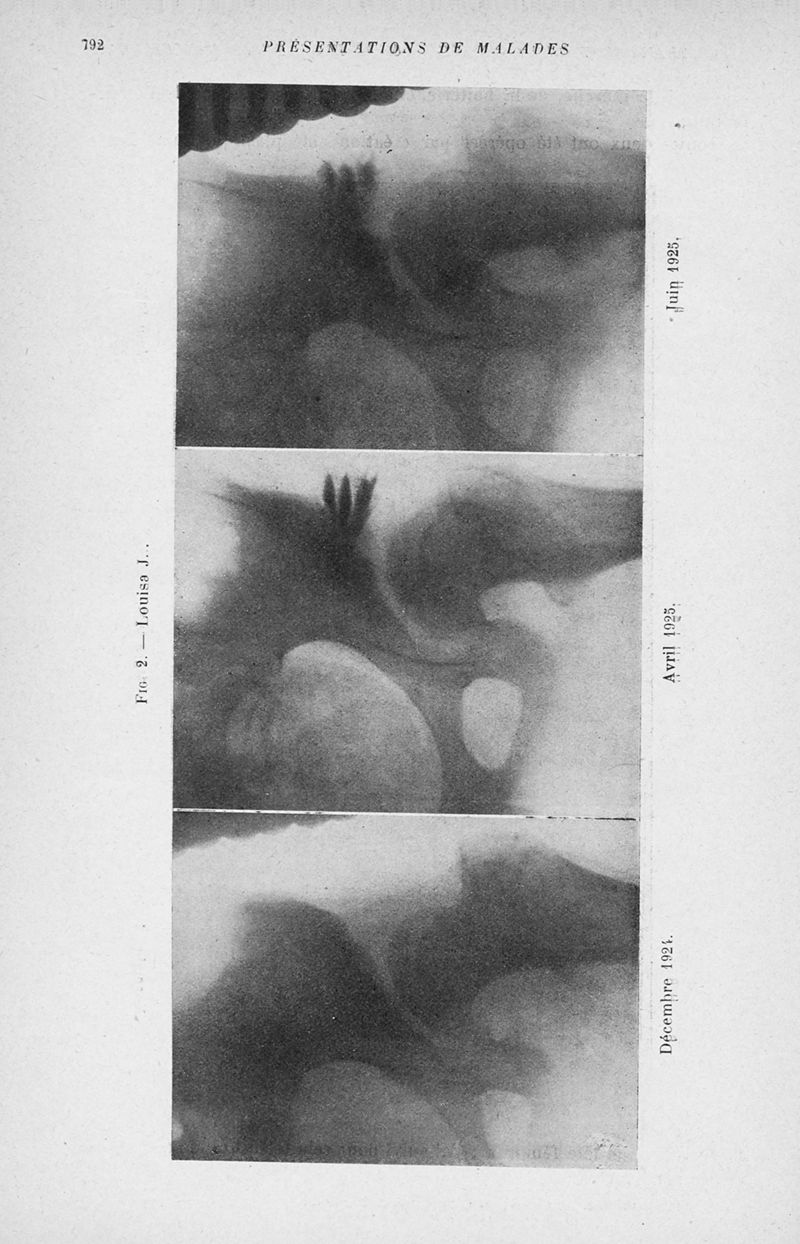

Bulletins et mémoires de la société nationale de chirurgie

Tome LI, 1925. - Paris : Masson, 1925.